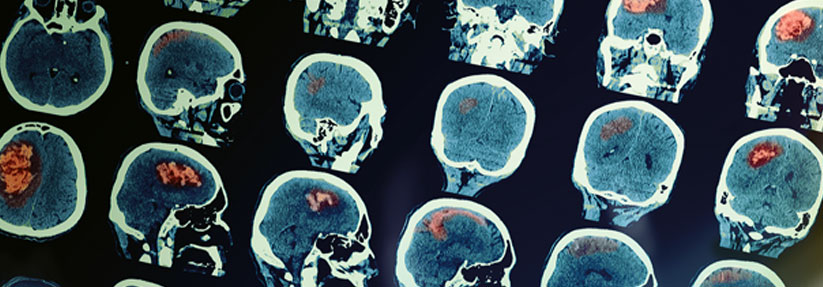

Lässt sich die hohe Toxizität bei Bestrahlung des Gehirns reduzieren? Lässt sich die hohe Toxizität bei Bestrahlung des Gehirns reduzieren? © fotolia/benevolente

Mit welcher Methode soll nach der Entfernung von malignen Hirnläsionen bestrahlt werden: per Ganzhirnbestrahlung oder mit dem Cyberknife? Zum Vergleich der onkologischen Sicherheit und kognitiven Ergebnisse gab es bisher keine qualitativ hochwertigen Daten.

Wenn resektable solitäre Hirnmetastasen von malignen Tumoren entfernt worden sind, gilt eine Ganzhirnbestrahlung bisher als Standard zur Verbesserung der intrakraniellen Tumorkontrolle.

Wegen ihrer kognitiven Toxizität gibt es aber immer wieder Bestrebungen, sie durch andere prophylaktische Maßnahmen zu ersetzen, darunter vor allem eine Behandlung der Operationshöhle mittels stereotaktischer Radiochirurgie.